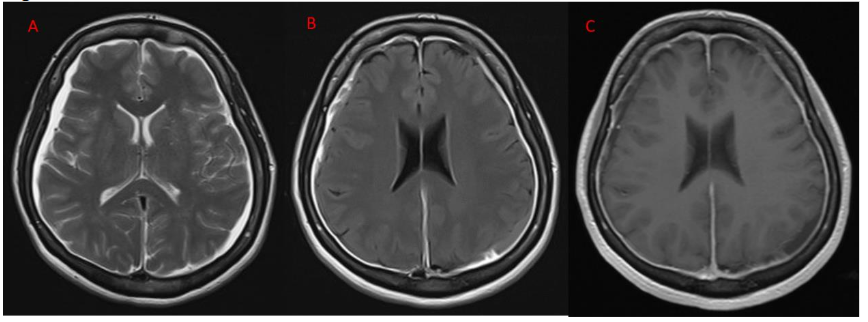

Her routine blood investigations including blood counts, liver and renal function tests were normal. Serum vitamin D and vitamin B12 levels were normal. CT brain and CT cerebral angiography was done in emergency to rule out any pituitary apoplexy, subarachnoid hemorrhage, vascular aneurysm, or vascular malformation, which was normal. Gadolinium-enhanced magnetic resonance imaging (MRI) showed bilateral subdural effusion, with diffuse smooth pachymeningeal enhancement (Figure 1). There was drooping of splenium of corpus callsosum, sagging of the midbrain, reduced mammillo-pontine distance, and pituitary hyperaemia. MRI of the spine showed smooth dural enhancement of the cervical and thoracic region. No CSF leak was noted in the contrast images. MR venogram showed engorgement of the venous sinuses. The imaging findings were in countenance with SIH (Figure 2). Ultrasound of the thyroid showed mild diffuse thyroid enlargement, with mild increase in vascularity.

Figure 2A&2B- post contrast T1 weighted Sagittal and coronal images showing engorgement of venous sinuses, Figure 2C- sagittal T2 weighted image showing sagging of mid brain (white arrow), dropping of splenium of corpus callosum (yellow arrow) and reduced mamillo- pontine distance (red arrow). Figure 2D – sagittal contrast enhanced T1 weighted images showing pituitary hyperaemia.